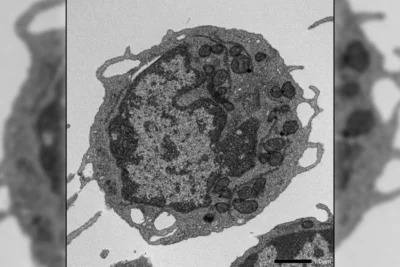

A “death” protein may be the key to slowing aging at its source